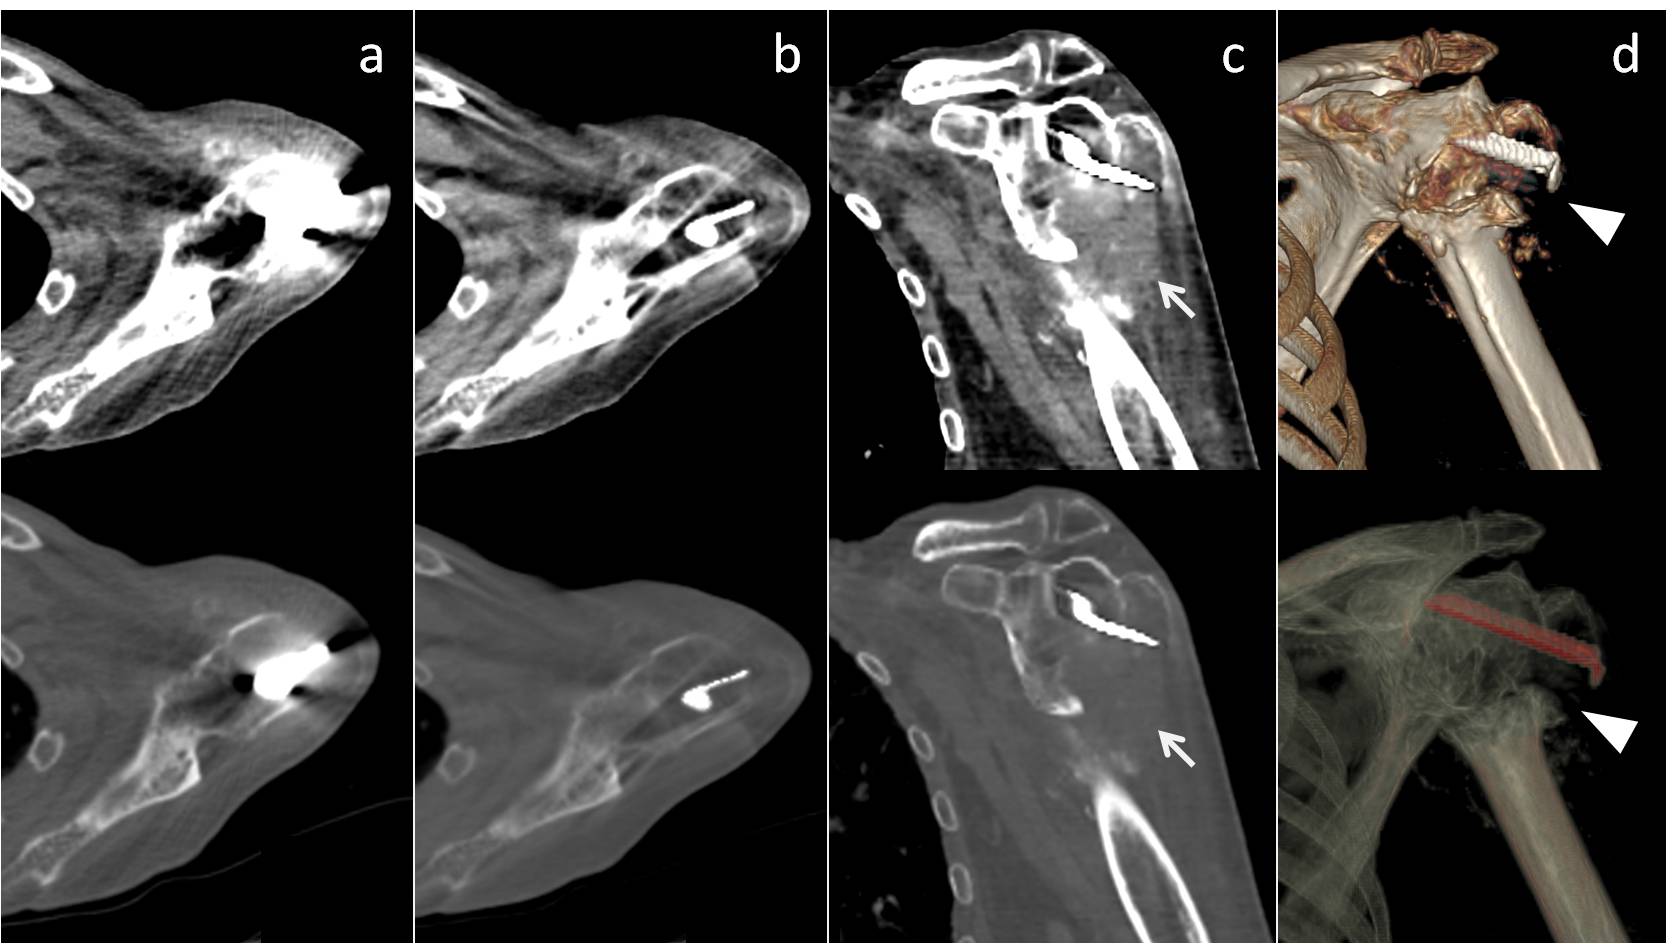

3. Bamberg F, Dierks A, Nikolaou K, Reiser MF, Becker CR, Johnson TR. Metal artifact reduction by dual energy computed tomography using monoenergetic extrapolation. European radiology. 2011;21:1424-1429

4. Pessis E, Campagna R, Sverzut JM, Bach F, Rodallec M, Guerini H, Feydy A, Drape JL. Virtual monochromatic spectral imaging with fast kilovoltage switching: Reduction of metal artifacts at ct. Radiographics : a review publication of the Radiological Society of North America, Inc. 2013;33:573-583

5. Mangold S, Gatidis S, Luz O, Konig B, Schabel C, Bongers MN, Flohr TG, Claussen CD, Thomas C. Single-source dual-energy computed tomography: Use of monoenergetic extrapolation for a reduction of metal artifacts. Investigative radiology. 2014;49:788-793

6. Wang Y, Qian B, Li B, Qin G, Zhou Z, Qiu Y, Sun X, Zhu B. Metal artifacts reduction using monochromatic images from spectral ct: Evaluation of pedicle screws in patients with scoliosis. European journal of radiology. 2013;82:e360-366

14. Lee YH, Park KK, Song HT, Kim S, Suh JS. Metal artefact reduction in gemstone spectral imaging dual-energy ct with and without metal artefact reduction software. European radiology. 2012;22:1331-1340

15. Lewis M, Reid K, Toms AP. Reducing the effects of metal artefact using high kev monoenergetic reconstruction of dual energy ct (dect) in hip replacements. Skeletal radiology. 2013;42:275-282

17. Guggenberger R, Winklhofer S, Osterhoff G, Wanner GA, Fortunati M, Andreisek G, Alkadhi H, Stolzmann P. Metallic artefact reduction with monoenergetic dual-energy ct: Systematic ex vivo evaluation of posterior spinal fusion implants from various vendors and different spine levels. European radiology. 2012;22:2357-2364